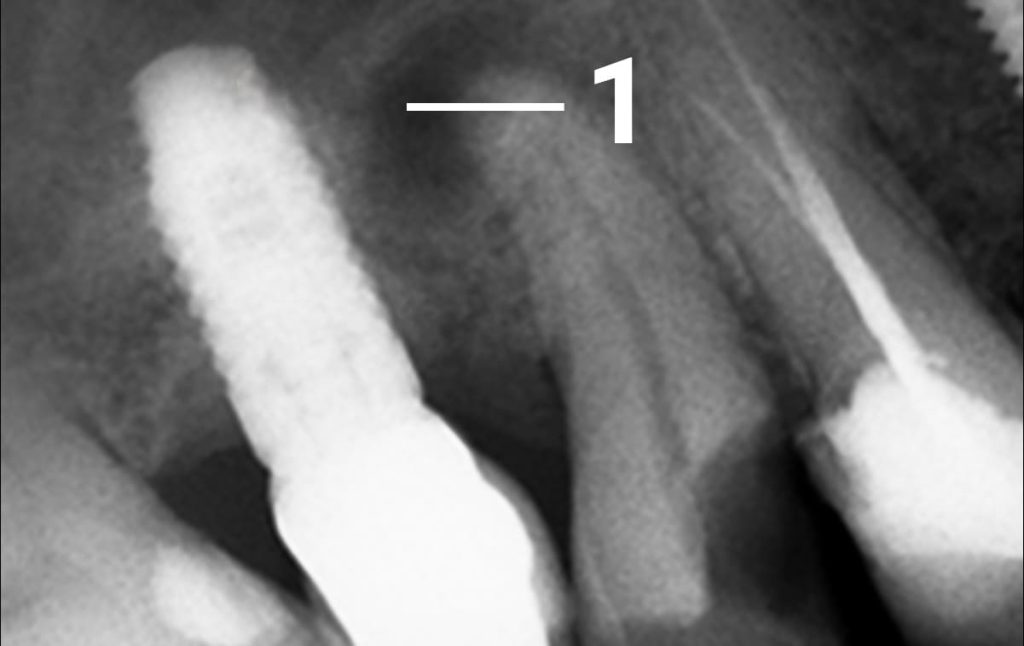

1. The clinic was contacted by a patient who had a long-term dental issue. X-ray analysis showed the presence of a long-standing inflammation at the apex of a root, which appeared in the picture as a dark spot with a clear outline. Previously, this issue would have been resolved by a removal of the tooth in question. 1 – the central point of damage with clear contours